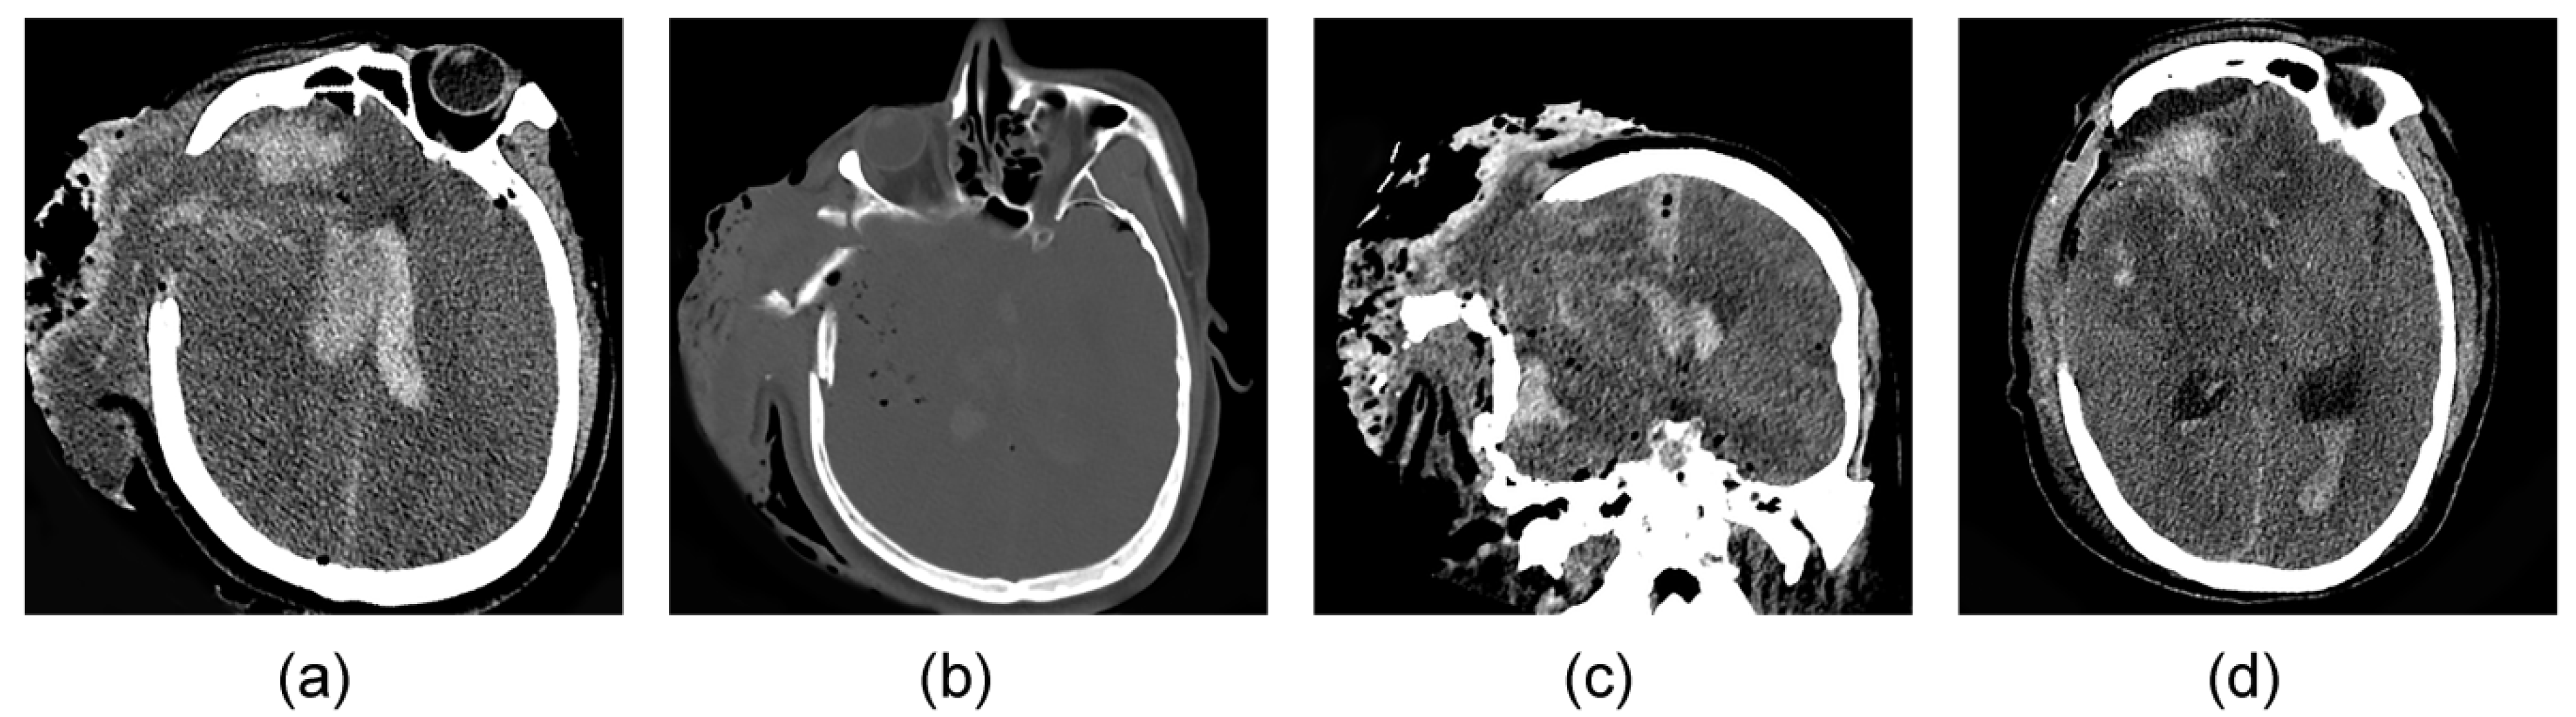

4. Data Collection